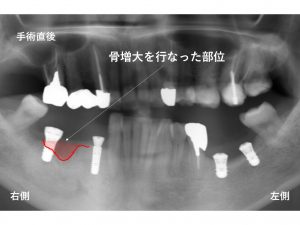

以下が先日行なったインプラント手術直後です。

下顎右側の奥歯は、骨吸収が大きかったので

骨の増大治療(GBR法)を行いました。

左側もいくつかの問題があったため、

工夫しながらの手術でした。

下顎左側の2本のインプラントのうち、

手前側は、真直ぐにインプラントが埋入されています。

しかし、奥歯は斜めになっています。

この理由ですが、

もし、真直ぐにインプラントを埋め込むと…

奥歯が斜めになっているため

埋め込む際に奥歯に器具がぶつかってしまいます。

型取り時にもぶつかってしまう

そのため、意図的に斜めに埋め込むことにしました。

また神経の管が通っているため

短いインプラントとなっています。